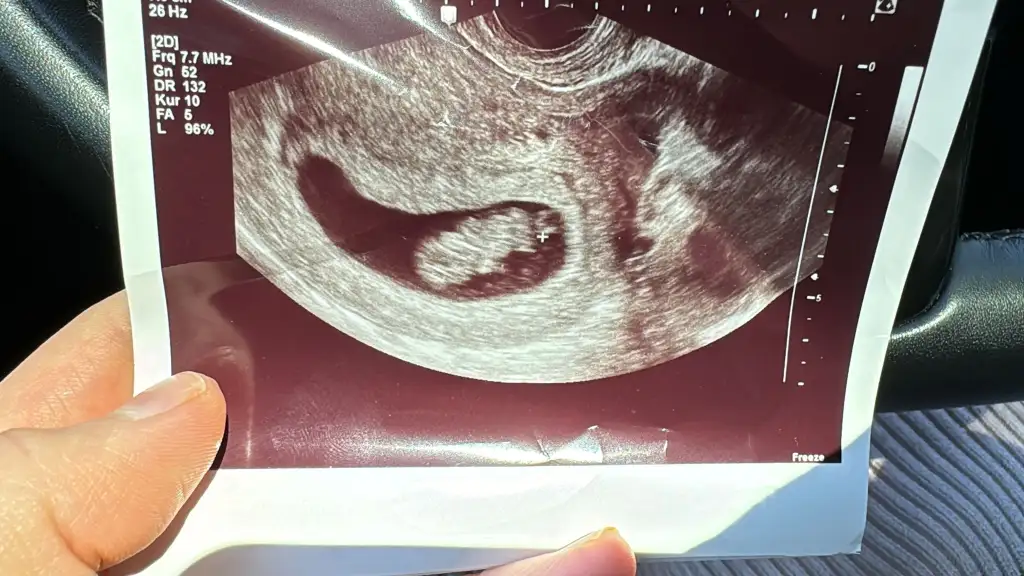

Merhaba 8+2 vajinal muayene sizce cinsiyeti nedir

Kıza benziyorKızlarr benimkinin cinsiyetini de tahmin edebilir misiniz biraz küçük ama merak iştekarından ultrason sat 6-6 doktora göre 6-3